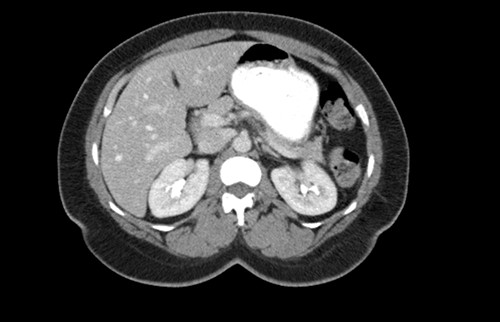

CT scan of the abdomen showing the absence of the gallbladder within the gallbladder fossa. This image also depicts the absence of malrotation of the gut or horseshoe kidney.

agenesis as seen in Fig. 1. The port sites were sutured closed, and no post-operative complications were noted. It was concluded that the adhesions were causing the patient’s chronic abdominal pain which resolved. A computed tomography (CT) scan of the abdomen seen in Figs 2 and 3 confirmed the absence of a gallbladder with no associated pathology depicted.

Gallbladder agenesis is a rare anomaly in which an individual is born without a gallbladder. This phenomenon affects <0.1% of the population with only 400 cases documented in medical literature to this day [2, 3]. This anomaly is discovered incidentally during workups for symptoms consisting of gallbladder pathology as seen in our patient. Initial work up for a gallbladder pathology includes a right upper quadrant ultrasound and, in this patient, it showed a collapsed gallbladder around gallstones, as seen in Fig. 4. This pointed to a diagnosis of cholecystitis. A further look with a HIDA scan confirmed this diagnosis as it showed the absence of radiotracer entering the gallbladder even after the administration of morphine, seen in Figs 5 and 6. A non-visualized gallbladder typically occurs due a gallstone obstructing the passage of the radiotracer entering the gallbladder [4]. Gallbladder agenesis could cause this radiographic finding as well, however, this anomaly was low in our differential as the initial ultrasound showed a collapsed gallbladder and the patient’s absence of other medical conditions associated with gallbladder agenesis, such as Klippel–Feil syndrome, horseshoe kidney, malrotation of the gut or aberrant left pulmonary artery, none of which were suspected in our patient seen on examination and radiographically [1]. The normal location of the gallbladder is located on the undersurface of the liver, aligning with the intrahepatic line that separates the right and left hepatic lobe. There was no sign of this organ once the liver was elevated, seen in Fig. 1. The likely cause of this patient’s chronic right sided abdominal pain were the multiple abdominal adhesions, which were lysed.